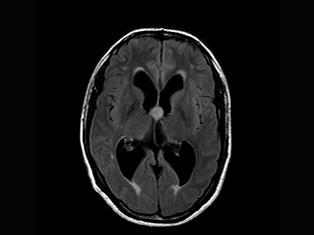

Cerebro Vascular

A stroke occurs when the blood supply to part of your brain is interrupted or reduced, preventing brain tissue from getting oxygen and nutrients. Brain cells begin to die in minutes. A stroke is a medical emergency.